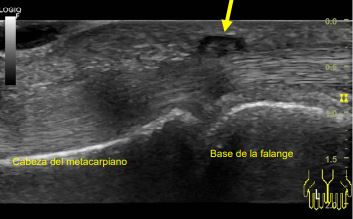

Hallazgos ecográficos

Se visualiza engrosamiento hipoecoico difuso en polea A1, líquido en las inmediaciones del tendón y tendón tumefacto.